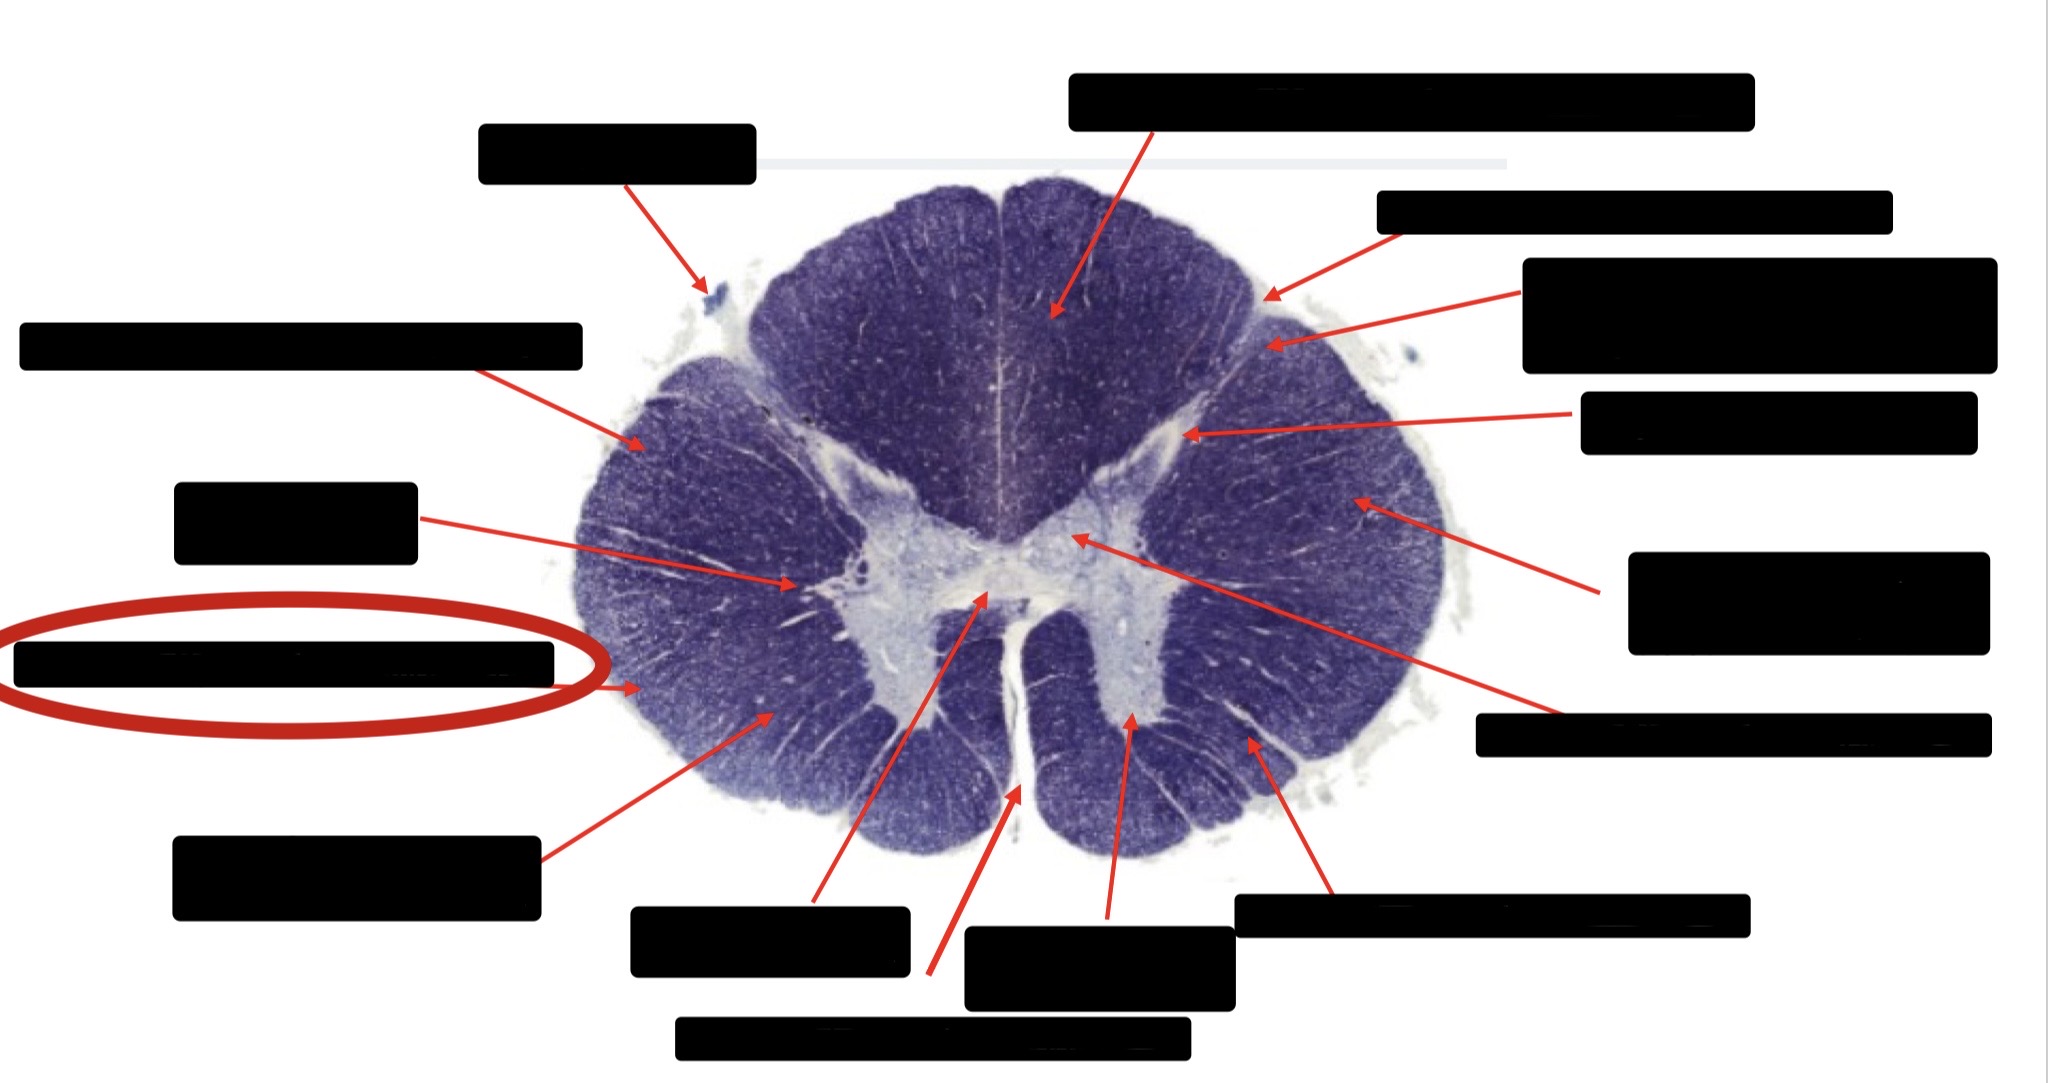

Spinothalmic Tract

Central Canal

Posterior Column (Fasciculus Gracilis)

Large Fiber Entry Zone

Lissaeur’s Tract & Small Fiber Entry Zone

Substantia Gelatinosa

Lateral Corticospinal Tract

Ventral Root Fibers

Anterior Horn Motor Neurons

Anterior Medial Fissure

Dorsal Rootlet

Posterior Spinocerebellar Tract

Anterior Spinocerebellar Tract